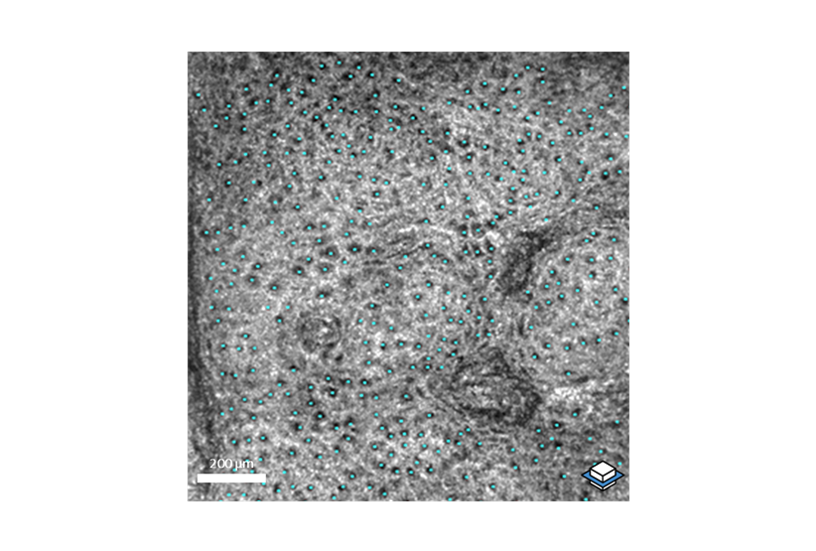

deepLive™ integrates LC-OCT (Line-field Confocal Optical Coherence Tomography) technology which provides a unique 3D imaging modality, allowing the user to switch from a histology-like vertical mode to a confocal-like horizontal mode,

and to record a 3D stack of tissue volumes in situ.

Navigations in LC-OCT™ 3D stacks

LC-OCT™ imaging of the back of a hand